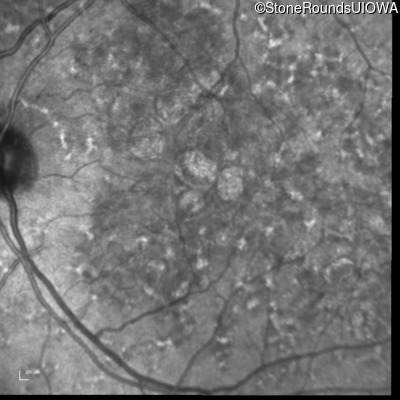

Age at visit: 49 years

OD OS

This 49 year old man was first told he had a fundus abnormality on a routine eye exam at age 34. Ten years later he noticed some distortion just superior to fixation.